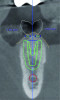

Fig 4. Digital tooth setup; the digital scan in Fig 2 was superimposed with a CBCT. The blue dots with green horizontal lines indicate MT measurements (2.04 mm and 2.02 mm). The simulated implant (green diagram of a dental implant with threads) and safety zone (green outline around the diagram of the implant) are overlaid on a cross-sectional image of the alveolar ridge. The red circle indicates the inferior alveolar nerve canal.

Figure 4

An example of an implant treatment planning case is presented in Figure 2 and Figure 4, with Figure 2 showing a digital scan of a mandibular arch that includes a missing tooth No. 19. The scan shows there was adequate KMW (>2 mm) at the No. 19 area. The digital scan of No. 19 was superimposed with a cone-beam computed tomography (CBCT) scan to analyze the future implant site. Upon superimposition, the MT could be measured at any surface (Figure 4). MT at the direct buccal and direct lingual aspects of the peri-implant mucosa was measured at >2 mm. The simulated future implant placement and the outlined safety zone of 1.5 mm radially and 2 mm apically around the implant indicate that the thickness of bone at the implant site was sufficient as planned. This case demonstrates there was enough KMW, bone thickness, and MT to proceed with implant placement.